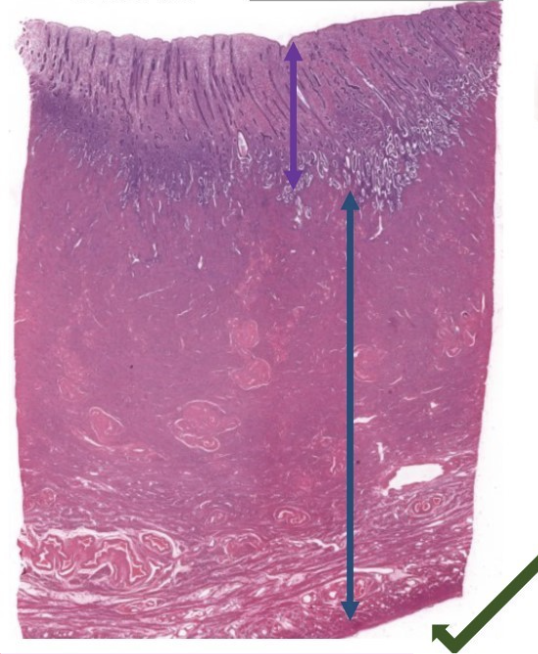

what is this slide

top = stratum functionale

bottom = stratum basale

endometrium of uterus